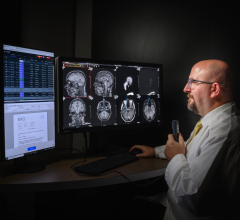

January 3, 2011 – Prime Radiology has selected Viztek to supply integrated radiology IT products and computed radiography (CR) hardware for a new imaging center in Edison, N.J. The multi-modality site, which will have five radiologists, will install Viztek’s Opal-RAD Web-based PACS, Opal-RIS Web-based RIS and billing software.

“We plan to read exams from multiple locations and to communicate images and reports electronically to referring physicians,” said Suresh Mody, M.D., president of Prime Radiology. He noted that in addition to CR, the center will also offer computed tomography (CT) and ultrasound exams as well as digital mammography, echocardiology and bone densitometry. “As a new center, we needed to purchase and install a large amount of technology at one time. Viztek offered us a fully integrated state-of-the-art system that fit our budget that made sense to purchase and install it immediately.”

The application suite and CR will be installed fully integrated and will include a built-in voice recognition system.